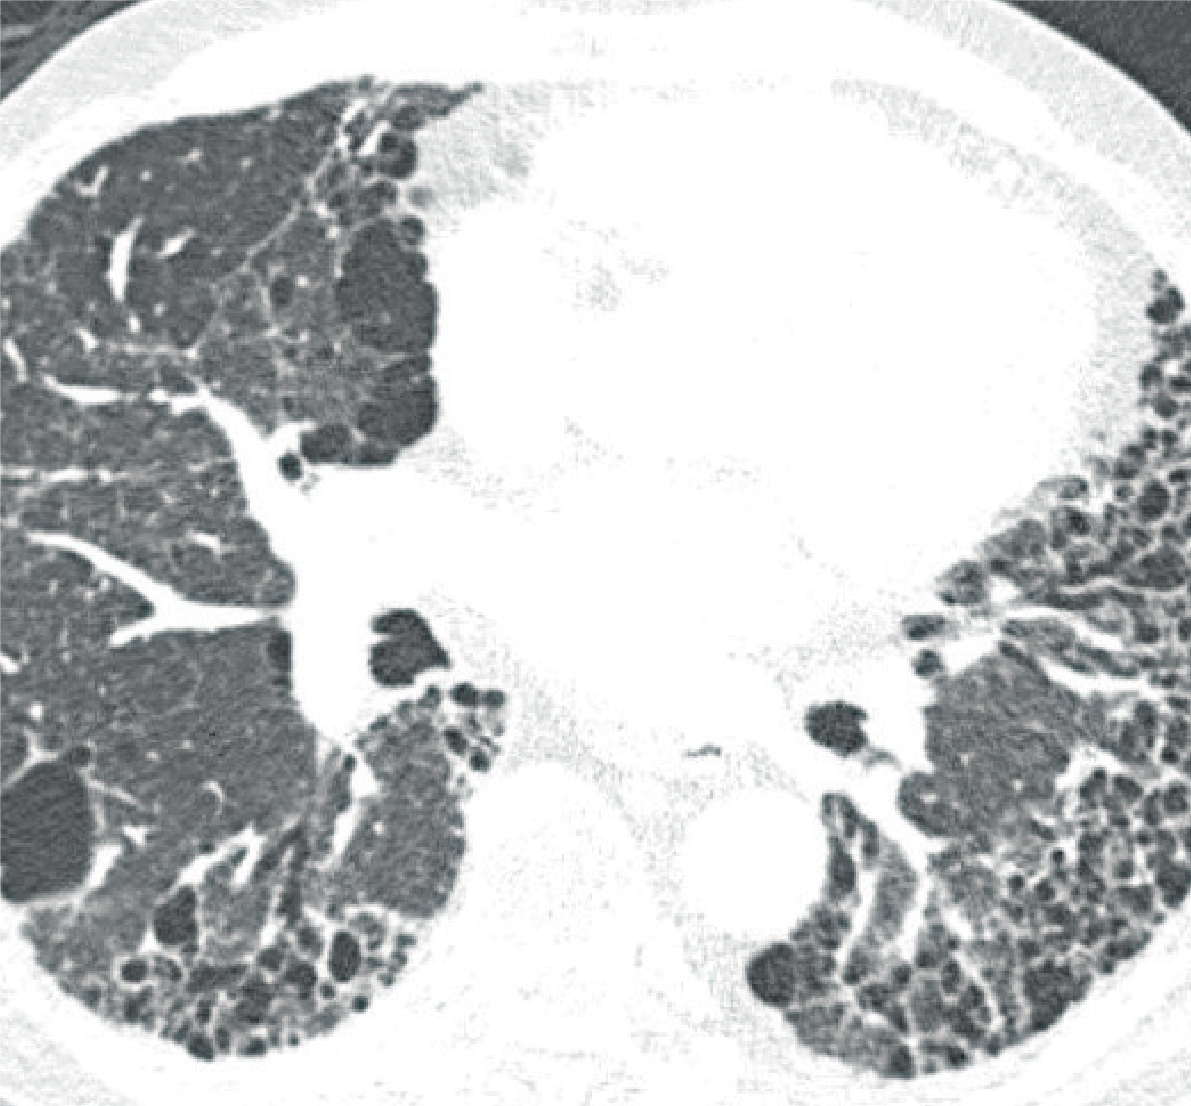

Een HRCT-scan maakt gebruik van röntgenstraling en een computer om zeer scherpe beelden van extra dunne doorsneden van de longen te kunnen maken. In tegenstelling tot de traditionele röntgenfoto van de borstkas, kunnen met behulp van een HRCT-scan vele kleine details in de longen zichtbaar worden gemaakt die behulpzaam kunnen zijn bij het stellen van de diagnose.

HRCT-scan van de borstkas